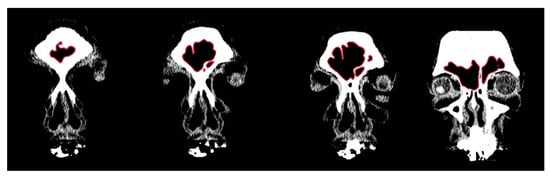

2.1. Morphological Analysis

3.1. Shape Variation Analysis